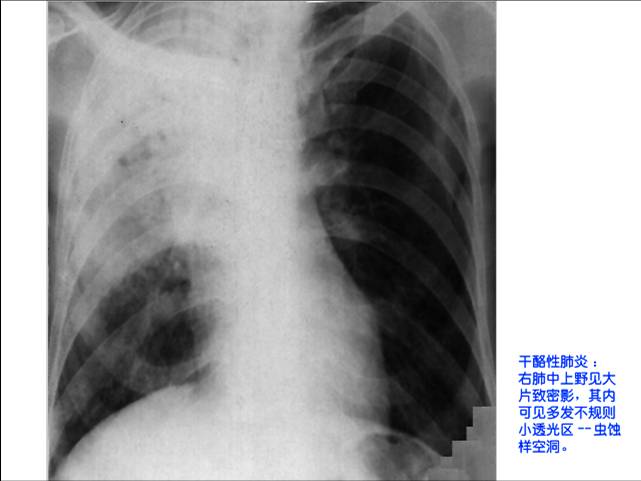

照片名称:干酪性肺炎